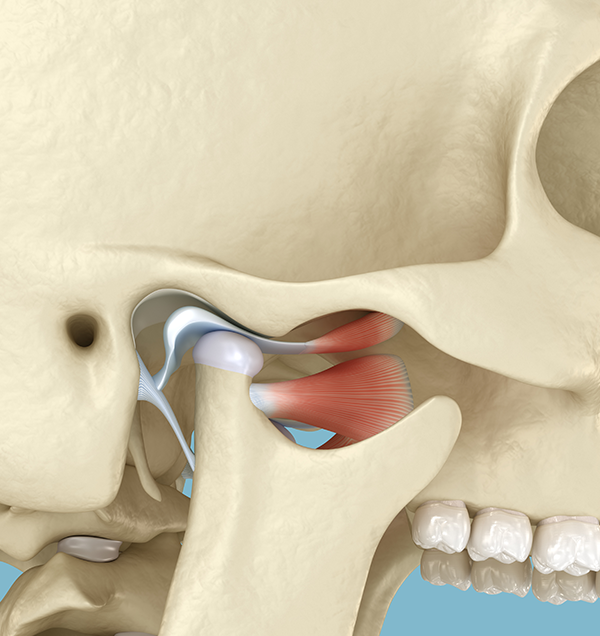

교정이 필요한 환자들의 상당수는 턱관절 문제가 동반됩니다.

턱관절에 대한 면밀한 검사 없이 무턱대고 교정부터 한다면 교정의 결과가

좋지 못하거나 추후 심각한 턱관절 문제가 발생할 수 있습니다.

저희 치과에는 턱관절 전문가인 구강내과 전문의가

상주하고 있습니다.

세브란스 대학병원 출신의 턱관절&교정 전문의 2인

함께 환자분의 턱관절을 면밀히 체크하며

완벽한 교정 결과를 만들어냅니다.

• 틀어진 턱을 바로잡는

턱 교정치료

턱관절의 위치를 변화시켜 턱이 정중앙에

놓일 수 있도록 서서히 유도하는 치료입니다.